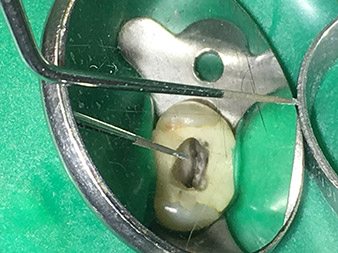

insert 4E

Préparation atraumatique du plancher cavitaire à l'aide de l'insert 4E.

L'insert 4E - cet instrument est optimal pour la préparation du plancher cavitaire, au niveau de la transition vers les canaux. Il peut être utilisé pour arrondir de manière optimale la transition entre le canal et le plancher cavitaire afin de produire un entonnoir qui conduit au canal. Par ailleurs, l'instrument est le choix idéal pour éliminer les surplombs dentinaires des canaux.

Globalement, la cavité peut être préparée de manière très efficace et minimalement invasive avec cet insert, en arrondissant et en lissant de manière optimale les débordements, les angles et les arêtes.